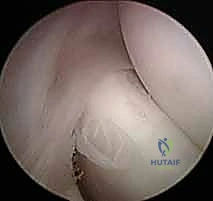

2. جراحة الكوع بالمنظار (Arthroscopic Tennis Elbow Release)

باعتباره رائداً في جراحة مناظير المفاصل في اليمن، يقدم الدكتور هطيف خيار الجراحة بالمنظار (بتقنية 4K عالية الدقة).

مميزات المنظار: